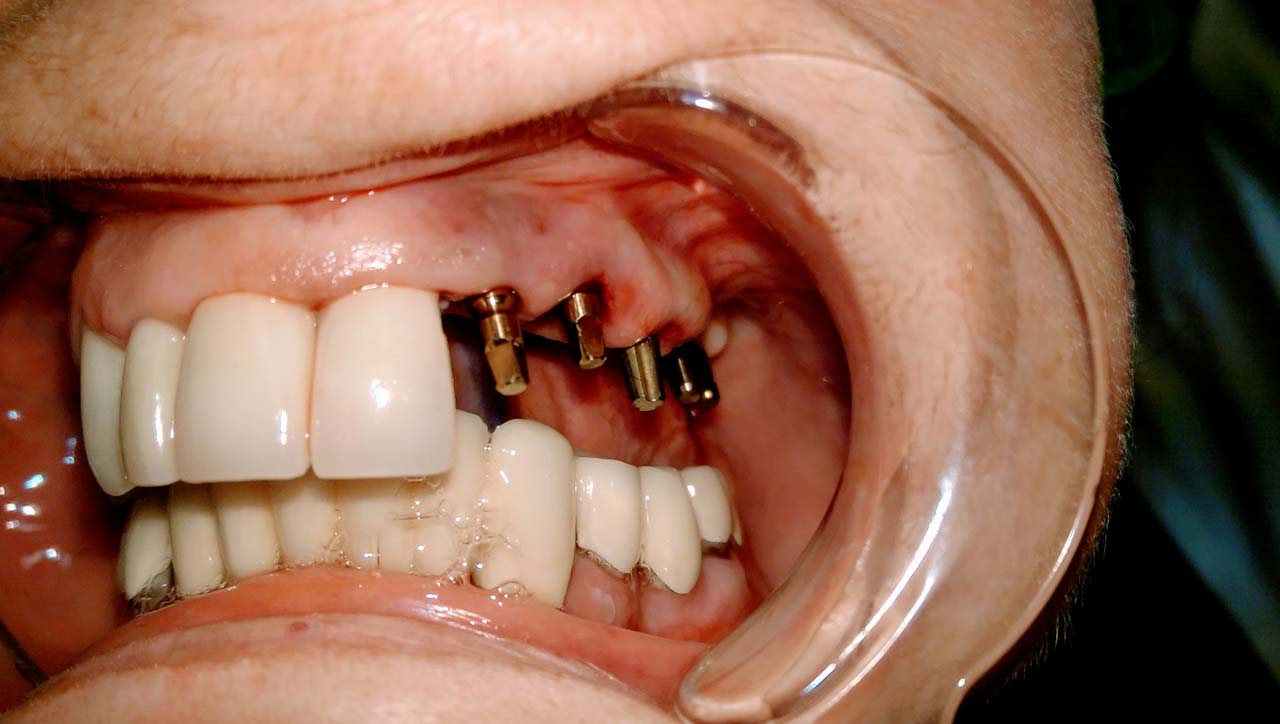

Teljes szájüregi rehabilitáció két lépésben

Ismét egy teljes szájüregi rehabilitáció két lépésben. Először az alsó fogak lettek kihúzva és azonnal implantálva, híddal ellátva, majd később a felső. IHDE svájci azonnal terhelhető implantátumok és cirkónium hidak. Dr. Kelemen Péter és a Symbion Fogtechnika közös munkája.